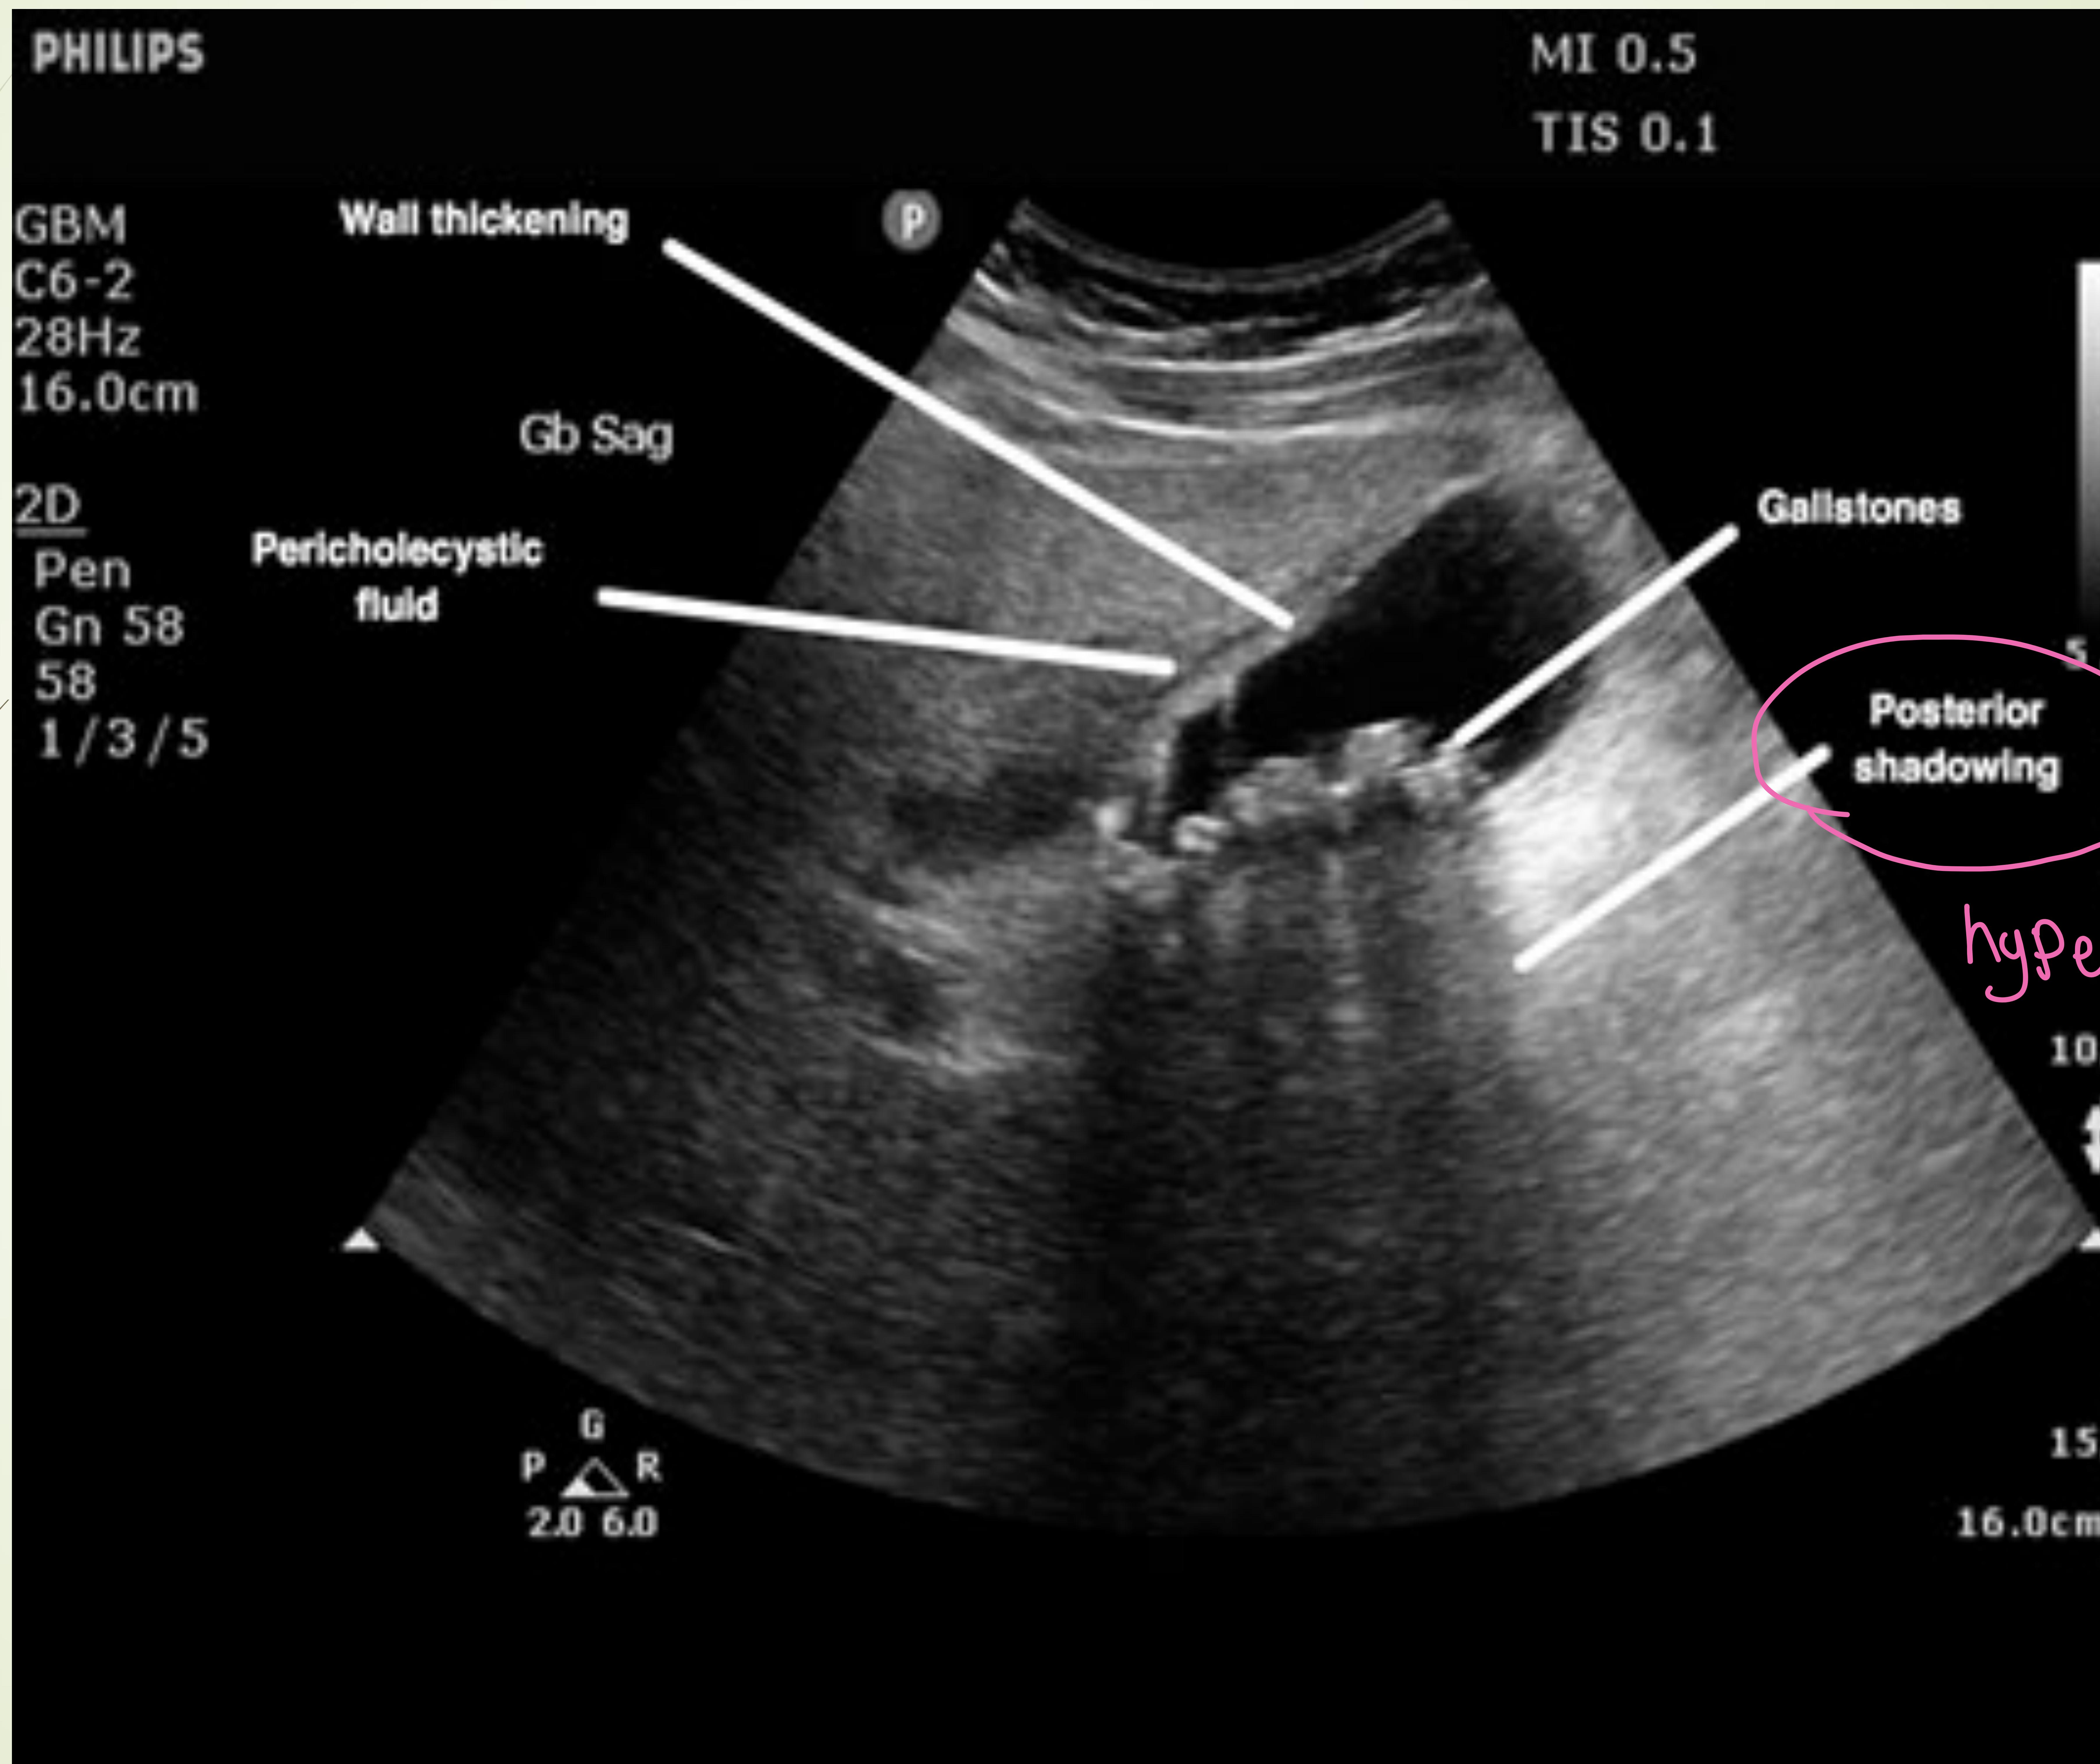

Case #5: Acute Cholecystitis

Presentation: 48yo Obese Female. RUQ pain after eating. Exam: +Murphy’s Sign.

- Gold Standard Image: RUQ Ultrasound (Thickened wall, fluid, stones, sonographic Murphy’s).

- Management: Antibiotics, Cholecystectomy.

Ultrasound showing gallbladder wall thickening and fluid.

Detailed US findings: Wall thickening, Pericholecystic fluid, Gallstones.